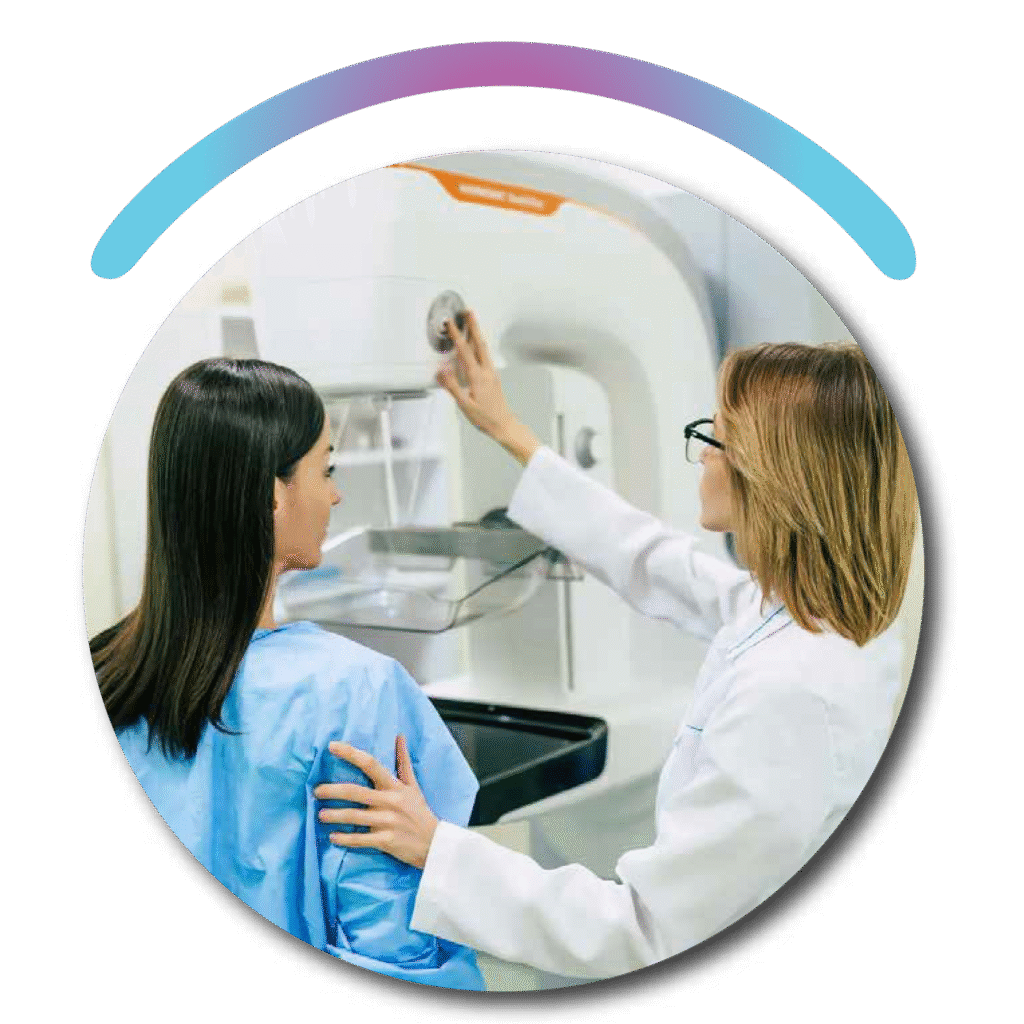

BREAST CANCER DETECTION

Our AI-powered Breast Cancer Detection solution analyzes mammograms with high accuracy to identify early signs of malignancy. It supports radiologists with faster, more reliable diagnostics—improving outcomes through early intervention.